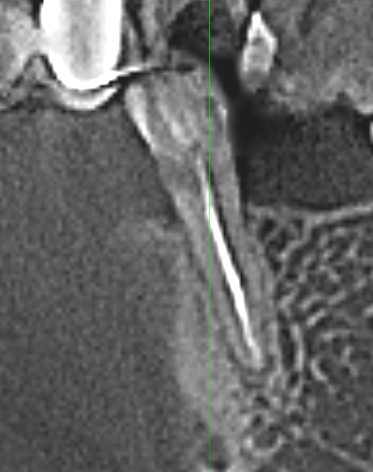

nau_63 Опубликовано 27 октября, 2025 Поделиться Опубликовано 27 октября, 2025 Добрый день. Нижняя 5-ка слева. Сильный клиновидный дефект. Зуб депульпирован и для прочности установлен штифт. Сбоку была пломба, но быстро отвалилась. При надавливании на зуб в сторону языка есть не сильная боль. Предполагаю, что при надавливании происходит изгиб в тонком месте и штифт смещается, вызывая боль. При жевании, вертикальном надавливании и надавливании наружу боль отсутствует. В кабинете протезирования предложили клиновидный дефект запломбировать, сразу зуб обточить (пока пломба не отвалилась) и поставить коронку. Прошу совета - будет ли в этом случае коронка прочно держаться и будет ли вся конструкция прочной при боковой нагрузке? Может быть есть другие варианты протезирования? Какой вариант (на Ваш взгляд) предпочтительней? Соседняя 6-ка отсутствует, планирую имплант. Ссылка на комментарий

nau_63 Опубликовано 1 ноября, 2025 Автор Поделиться Опубликовано 1 ноября, 2025 (изменено) Может быть, как вариант установить вкладку, а потом коронку? На однокоренной зуб вкладки устанавливают? Изменено 1 ноября, 2025 пользователем nau_63 Ссылка на комментарий

Doc Опубликовано 1 ноября, 2025 Поделиться Опубликовано 1 ноября, 2025 Эти срезы неинформативны. В целом вкладку можно установить на любой зуб, однокорневой, многокорневой — неважно, но информации маловато для того, чтобы что-то советовать конкретное. 1 Ссылка на комментарий

nau_63 Опубликовано 11 ноября, 2025 Автор Поделиться Опубликовано 11 ноября, 2025 В 01.11.2025 в 22:14, Doc сказал: Эти срезы неинформативны. В целом вкладку можно установить на любой зуб, однокорневой, многокорневой — неважно, но информации маловато для того, чтобы что-то советовать конкретное. У меня есть КТ. По нему можно сделать выводы? Ссылка на комментарий